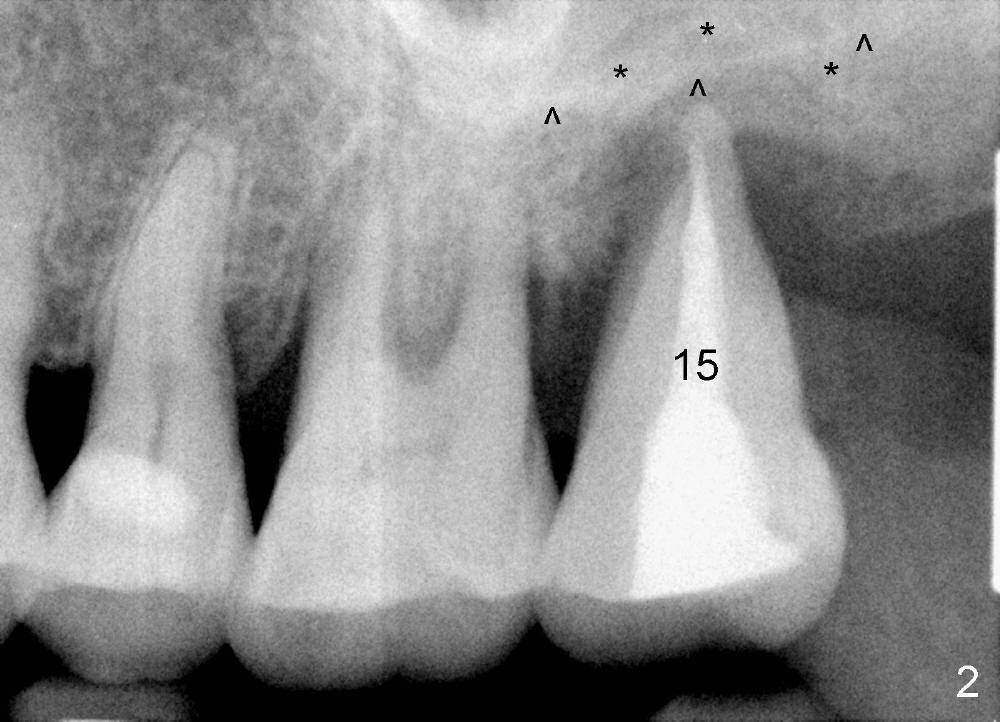

A 56-year-old female has recurrent infection and buccal gingival recession (Fig.1 *) after root canal therapy in the upper left 2nd molar (Fig.2). The extraction socket is single and large. Osteotomy forms by using a series of osteotomes (2-5 mm in diameter) mesiopalatal to the center of the socket. The sinus floor is thin (approximately 2-3 mm). The osteotomy is further enlarged by inserting 4.5-8 mm taps at the depth between 14 and 17 mm from the gingival margin. The last tap has barely achieved stability (Fig.3). It appears that the tap has almost obliterated the socket. Allograft is pushed into the sinus before placement of a 8x17 mm implant. The insertion torque is between 15 and 20 Ncm (Fig.4). The gingiva-level implant is slightly subgingival except buccal (Fig.5). To facilitate buccal gingival re-growth and cover the exposed implant surface, bone graft is placed subgingival (Fig.5 ^). The gingival sulcus is closed partially by placement of a thin strip of collagen membrane (not shown). The wound is protected by applying perio dressing.